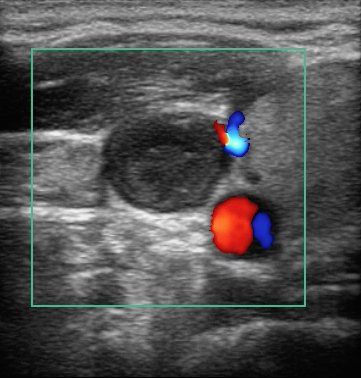

Bild: Vena jugularis, Thrombus